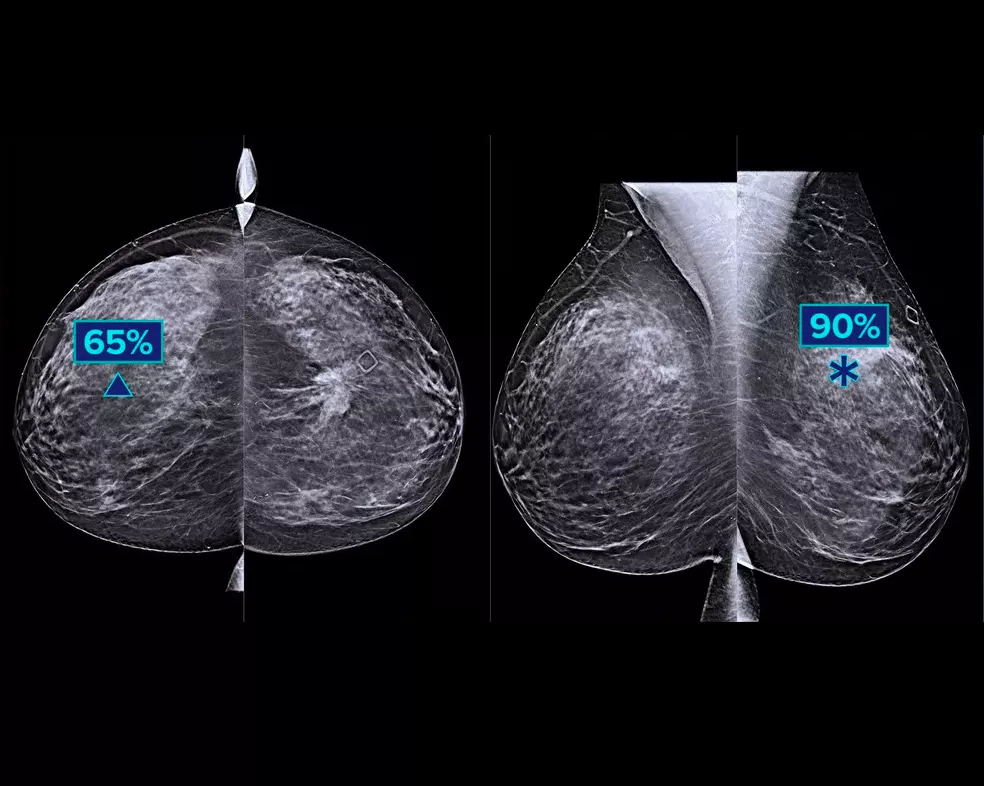

The algorithm looks for 3 main groups of suspicious lesions: calcifications, masses, densities and distortions, and any combination of these lesions. Outputs may vary on different reading workstations.

Integration on the acquisition workstation allows flagging of high-risk cases for immediate reading. Provides case-level metrics, helping categorise cases for priority reading.